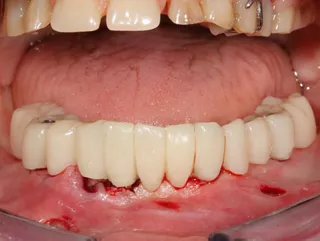

16. Display of the finished lower jaw work after osseointegration.